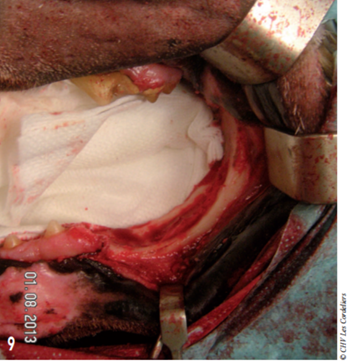

L’ostectomie allait en profondeur jusqu’au canal mandibulaire (photos 9 à 12).

Photo 9 : La dernière prémolaire et toutes les molaires ont été retirées avec l’ostectomie.

Celle-ci s’étend jusqu’au canal mandibulaire.